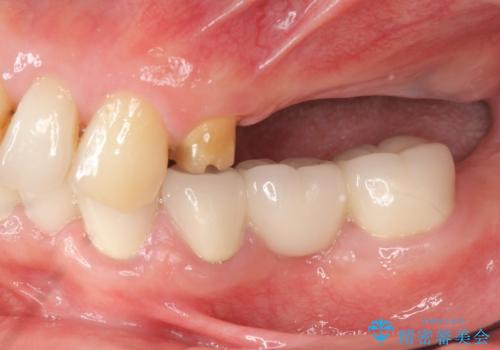

- 重度の虫歯により左上の歯を失い、インプラント治療は怖いため嫌厭して放置していたが、いよいよ食事に困りしっかりと噛めるようになりたいと希望され来院されました。

残存している小臼歯も虫歯が大きく保存が難しいため抜去を行い造骨を含めたインプラント治療を行います。

最終的なジルコニアクラウン装着後は、まるで自分の歯のように咬める、と咬合機能の回復を大変喜んでいただくことができました。